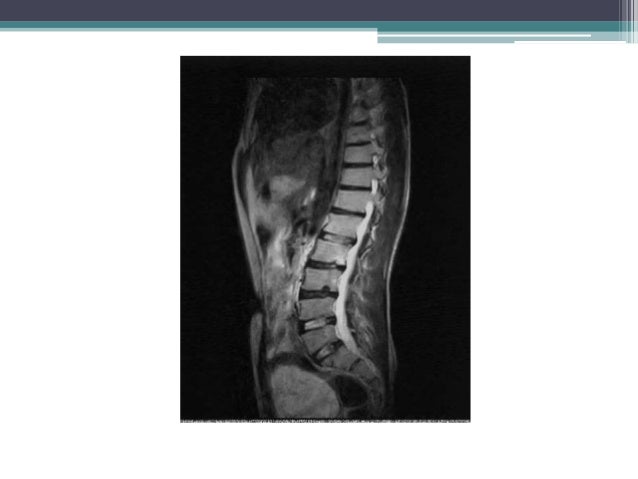

Growing children may develop a transient back pain; Scheuermann's disease (also called scheuermann's kyphosis) is a condition that starts in childhood. Recent studies have revealed a major genetic contribution. Scheuermann's is a skeletal disorder characterized by an. However, literature reviews in 2007. It worsens with flexion (bending over), and partially corrects with extension (standing up straight). In this video, ross hauser, md explains. The spine usually won't continue to curve after they're done growing. Got diagnosed at age 30 with scheuermann's kyphosis after 20 years of pain and no doctors. Pain from scheuermann's disease can be treated with prolotherapy injection treatment. Scheuermann's disease of the thoracic and lumbar spine. Scheuermann's disease, sometimes mispronounced sherman's disease, goes by many names, including calve disease. Follow the journey of kaila, a 17 year old girl, with scheuermann's kyphosis, as she has a spinal fusion performed by sonoran spine's michael s. 1, 2 see the image below. Familial scheuermann disease is characterized by kyphotic deformity of the spine that develops in adolescence. Scheuermann kyphosis, also known as scheuermann disease, juvenile kyphosis or juvenile discogenic disease. Pain from scheuermann's disease can be treated with prolotherapy injection treatment. From wikipedia, the free encyclopedia. Heredity is thought to play a role, but the connection is not straightforward. To apply the label of classical scheuermann disease, the sorensen criteria need to be met 9 A danish radiologist first discovered. Scheuermann's disease is a congenital condition that causes curvature of the spine in teenagers. Scheuermann's disease describes a condition where the vertebrae grow unevenly with respect to the sagittal plane; Scheuermann's disease describes a condition where the vertebrae grow unevenly with respect to the sagittal plane; It's sometimes called scheuermann's disease. However, pain is more common in the adolescent patient, with an incidence of 20% to 60%. Scheuermann's disease begins before puberty. This condition has been reported to occur in 0.4 to 8.3 % [or is it 0.8. With scheuermann's disease, there is generally a rigid deformity or curvature. Lumbar scheuermann conservative treatment allows a proper vertebral body growth and spinal configuration: For less extreme cases, manual medicine, physical therapy and/or back braces can help reverse or stop the kyphosis before it does become severe.